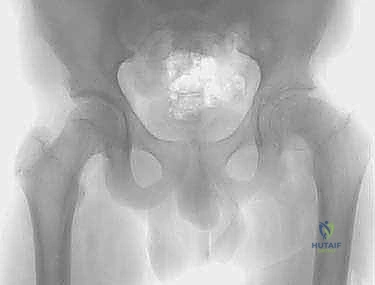

الخطوة الخامسة: التثبيت الصلب (Rigid Fixation)

للحفاظ على هذا الوضع الجديد حتى يلتئم العظم، يتم استخدام شرائح ومسامير معدنية قوية جداً. قديماً كانت تُستخدم الشريحة ذات الشفرة (Blade Plate)، ولكن اليوم، يستخدم الأستاذ الدكتور محمد هطيف أحدث أنظمة التثبيت العالمية مثل (Dynamic Hip Screw - DHS) أو الشرائح التشريحية المغلقة (Locking Plates) التي توفر ثباتاً مطلقاً وتسمح بالتئام أسرع.

الخطوة الرابعة: التدوير والتصحيح (Correction and Rotation)

بمجرد قطع العظم، يتم تدوير الجزء السفلي من عظم الفخذ (الساق) للأمام وللداخل ليصطف بشكل مثالي مع الجزء العلوي (الرأس والعنق). في هذه اللحظة، يختفي "تشوه قبضة المسدس" وتستعاد ديناميكية المفصل الطبيعية.